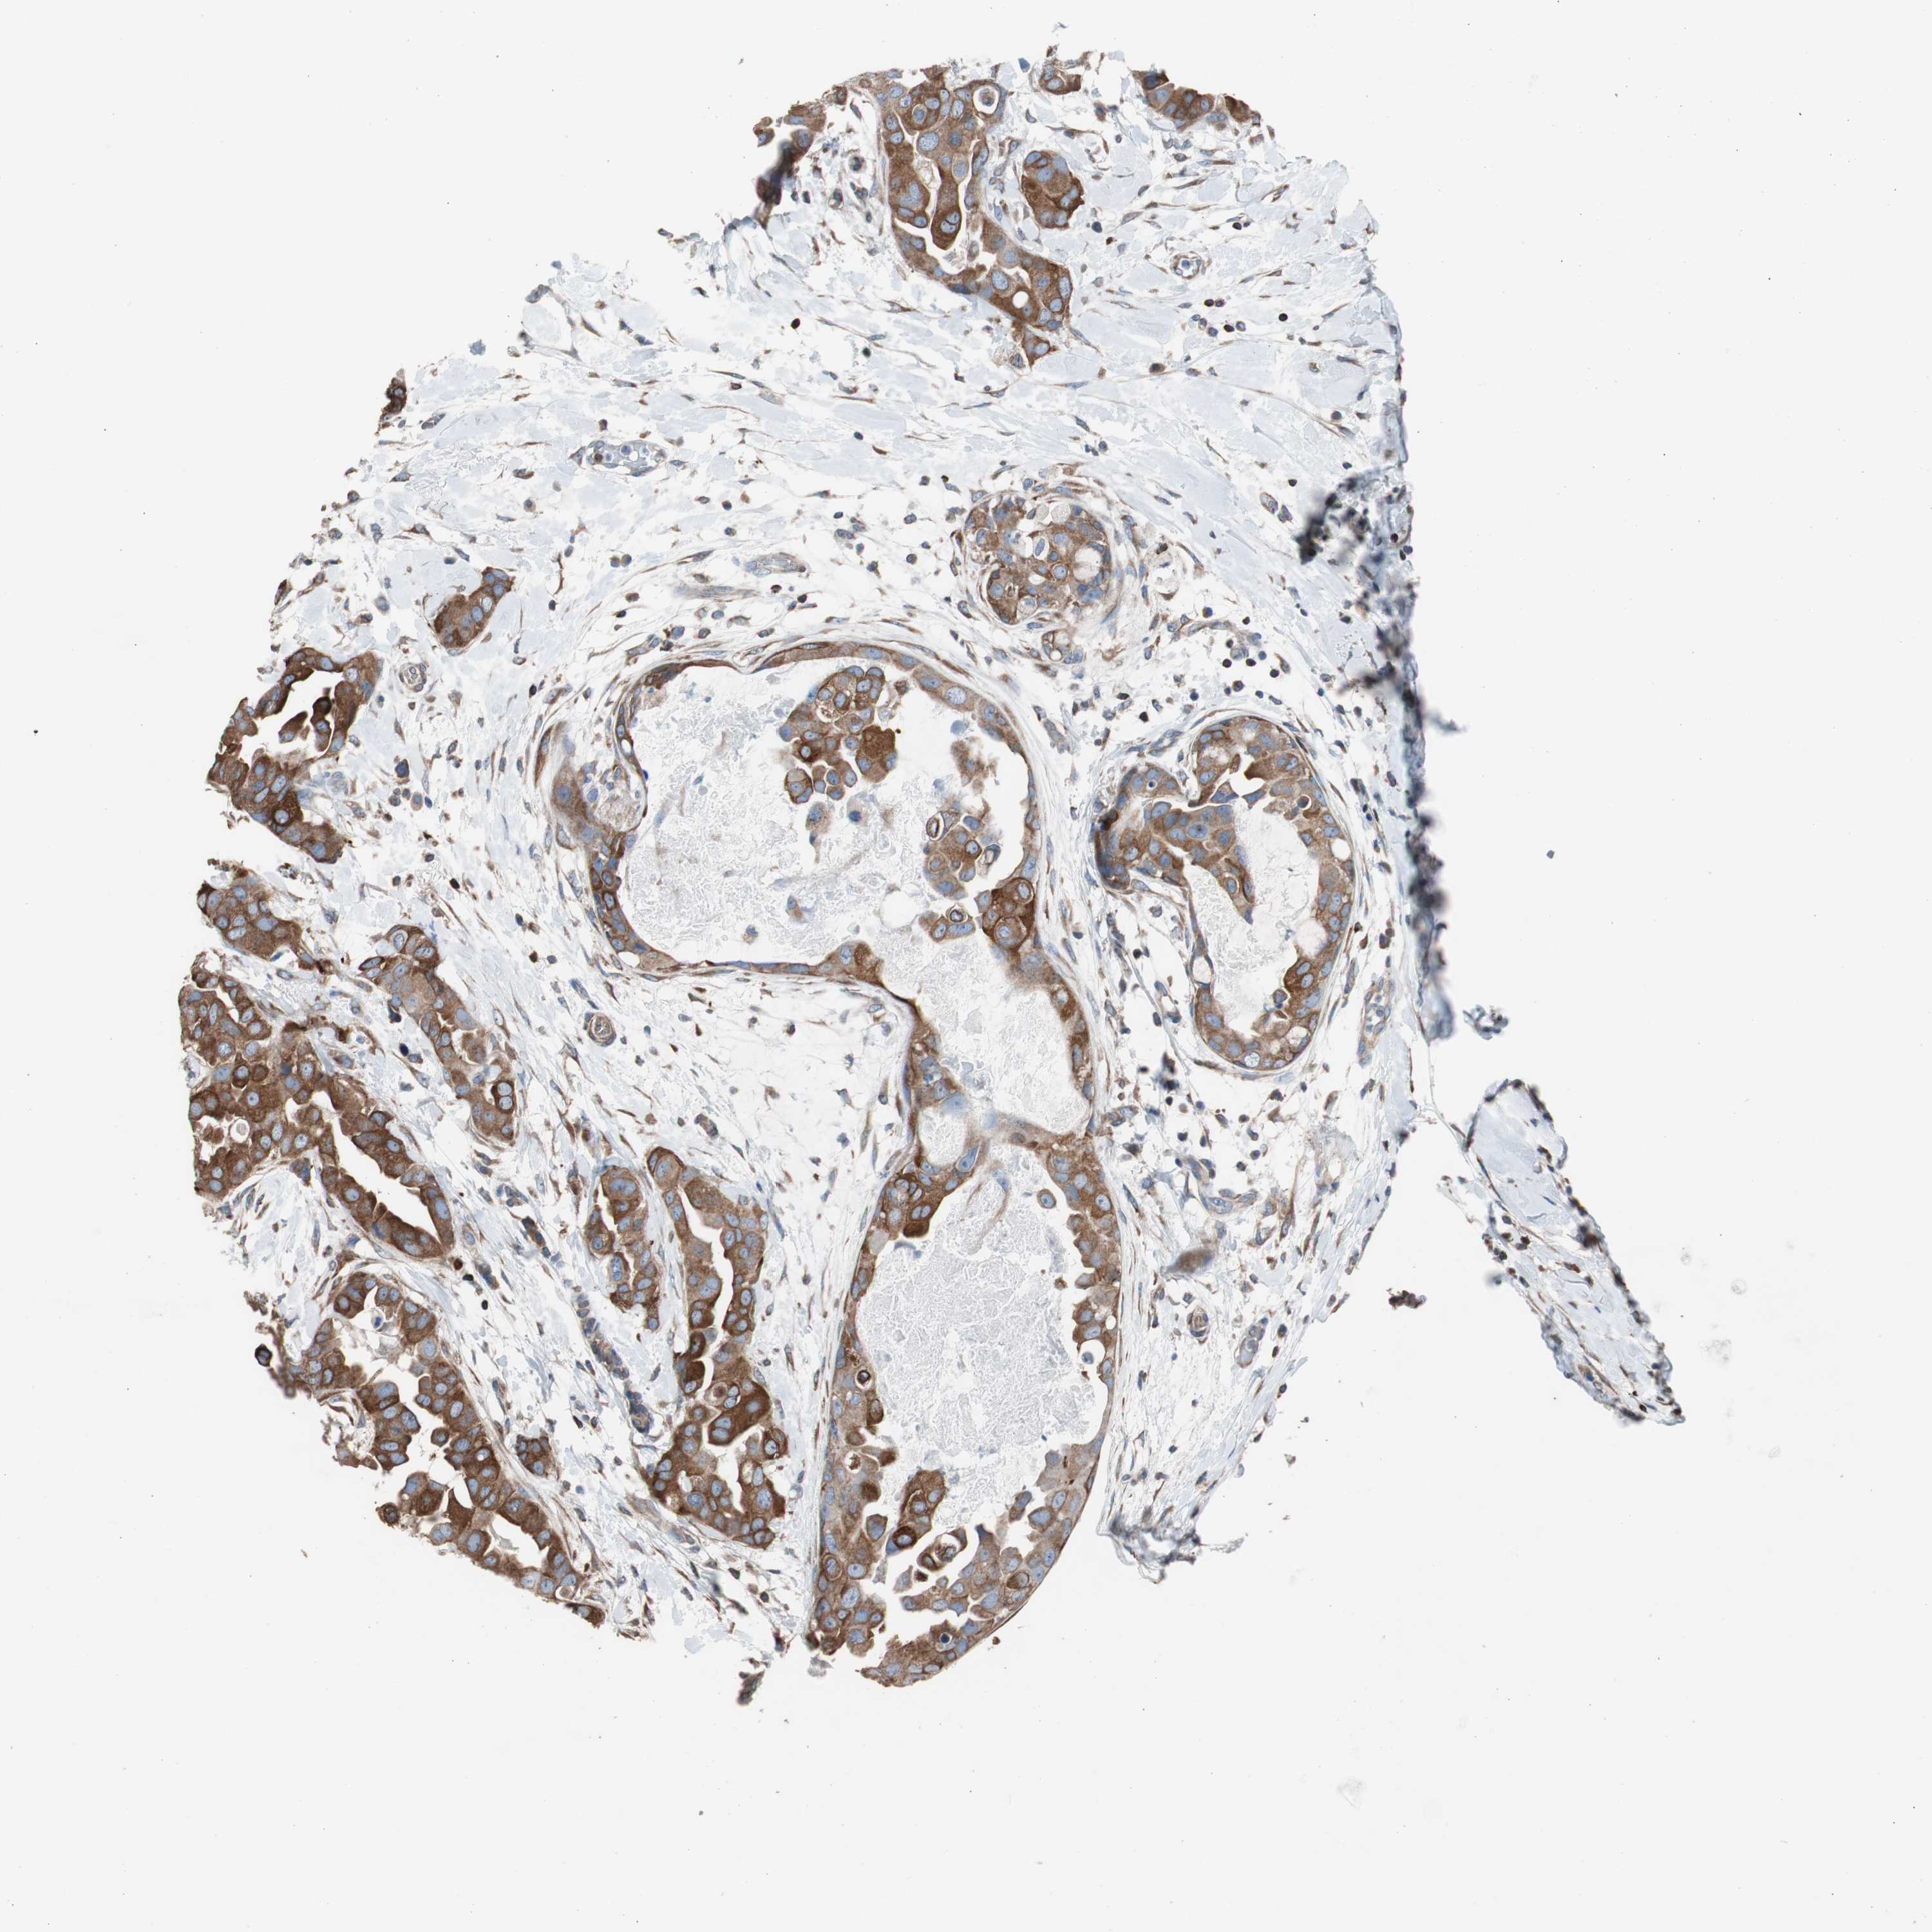

BRCA TCGA BRCA VALIDATION PROTEIN EXPRESSION

ANTIBODIES

AND

VALIDATION